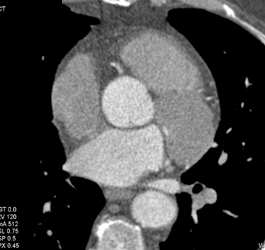

Diagnosis

Diseased LAD